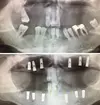

Implant tedavisi